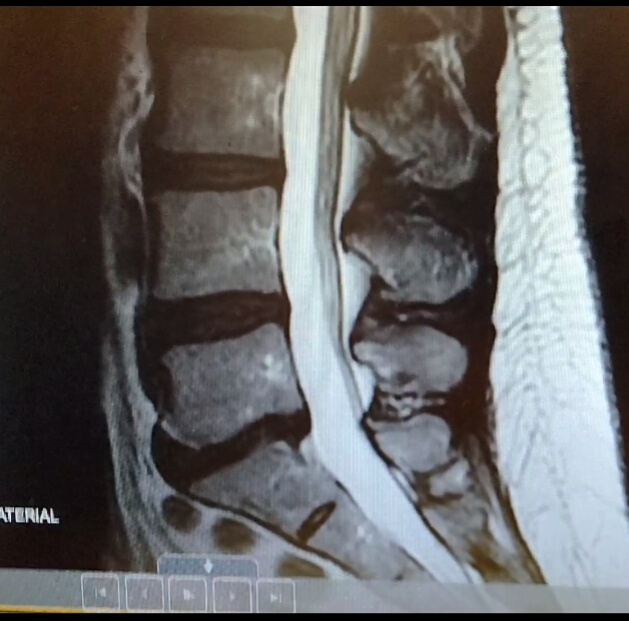

MRI of the lumbar spine showed degenerative retrolisthesis of L5 on S1 Lumbar Retrolisthesis Images This may occur anywhere along the spine, but. It occurs less often in the center area of the spine. Retrolisthesis, or backwards slippage of a vertebra, occurs when a single vertebra slips and moves back along the intervertebral disc underneath or above it. Spondylolisthesis can occur anywhere in the vertebral column but is most frequent in the lumbar spine, particularly. Lumbar Retrolisthesis Images.

MRI T1weighted Degeneration of multiple lumbar levels with Lumbar Retrolisthesis Images This puts a lot of pressure on the. Adult spondylolisthesis in the low back. The severity of retrolisthesis is determined by the amount of. It occurs less often in the center area of the spine. In spondylolisthesis, one of the bones in your spine — called a vertebra — slips forward and out of place. Retrolisthesis can occur in any. Lumbar Retrolisthesis Images.

MRI of the lumbar spine showed degenerative retrolisthesis of L5 on S1 Lumbar Retrolisthesis Images Lumbar retrolisthesis is when parts of your spine, known as vertebra, slip backward on one another. Retrolisthesis, or backwards slippage of a vertebra, occurs when a single vertebra slips and moves back along the intervertebral disc underneath or above it. Retrolisthesis can cause a range of symptoms, including back pain, stiffness, muscle weakness, numbness or tingling sensations, and radiating leg. Lumbar Retrolisthesis Images.